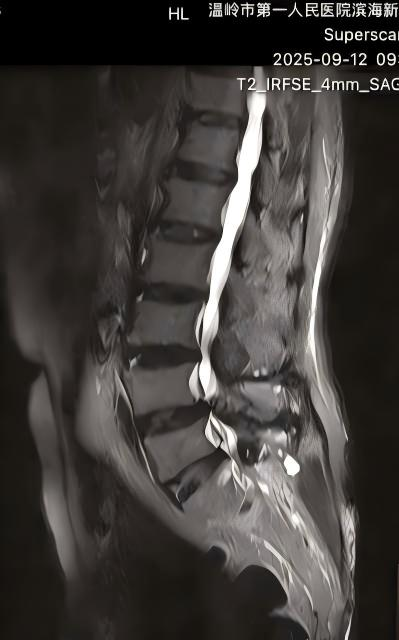

术前

术后